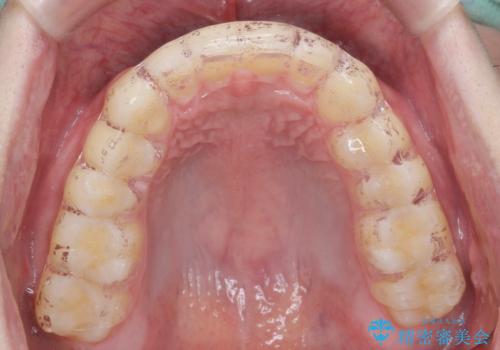

ナイトガードで歯ぎしり予防

- 歯ぎしりが気になるとの事で来院。

しっかりしたナイトガードが欲しいとの事だったので自費のナイトガードのご案内をしました。

ナイトガードは夜寝ている時、無意識に歯ぎしりをして歯がすり減ることを防ぐことがあります。また、歯が割れたり欠けたりするのも防いでくれます。